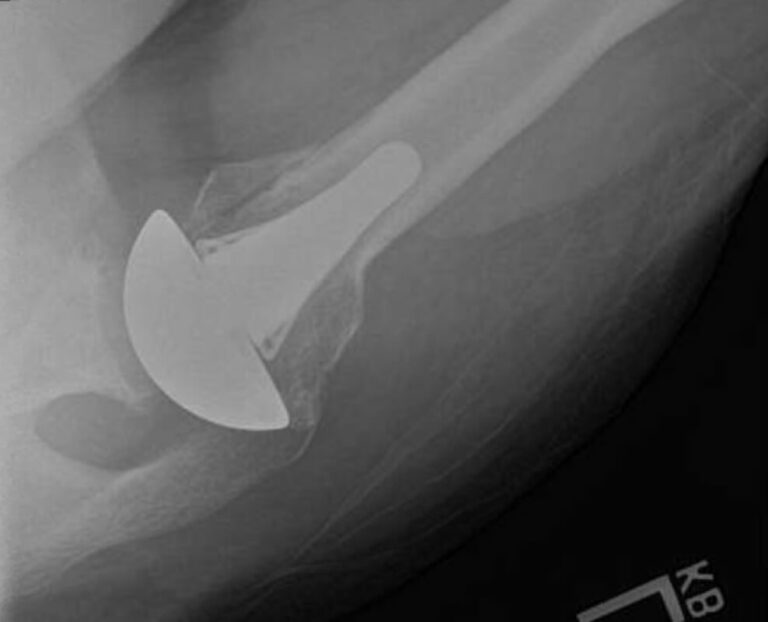

DJO/Enovis, Altivate